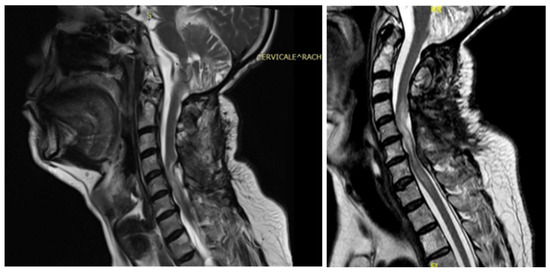

3.4.3. Case 3

3.4.4. Case 4

| Patient | 1 | 2 | 3 | 4 | 5 |

|---|---|---|---|---|---|

| Age | 46 | 48 | 62 | 43 | 68 |

| Gender | M | M | M | F | F |

| Level | T12–L2 | C5–C6 | T7–T10 | T8–T9 | T8–T11 |

| Location | Intramedullary | Intradural | Intradural–Extradural | Intramedullary | Intradural |

| Primary/secondary | Secondary | Secondary | Secondary | Secondary | Secondary |

| Numbness | Yes | No | Yes | Yes | Yes |

| Gait disturbances/ataxia | No | Yes | No | Yes | Yes |

| Lumbar pain | No | No | Yes | Yes | No |

| Urinary–bowel dysfunction | Yes | No | Yes | No | No |

| Limb weakness | Yes | Yes | No | No | No |

| Paraplegia | No | No | Yes | No | No |

| Sexual disfunction | Yes | No | No | No | No |

| Surgical treatment | lysis of adherences and syrinx cavity opening | resection of the cystic formation and adhesiolysis | resection of the cystic formation and adhesiolysis | resection of the cystic formation and adhesiolysis | resection of the cystic formation and adhesiolysis |

| Complications | CSF fistula | infection | None | CSF fistula | None |

| KPS pre-op (%) | 70 | 50 | 70 | 80 | 90 |

| KPS post-op (%) | 80 | 50 | 60 | 90 | 80 |

| ASIA score pre-op | C | B | B | C | D |

| ASIA score post-op | D | B | C | C | D |

| Follow-up (years) | 2 | 2 | 2 | 3 | 1 |